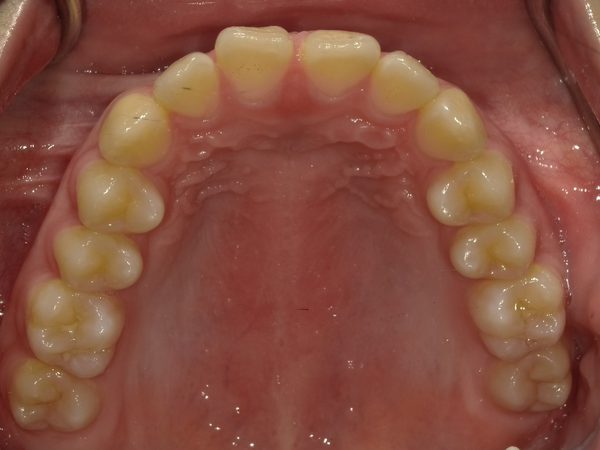

すきっぱ(空隙歯列)CASE5 2023.06.19 10代女性非抜歯〇ご相談内容:上前歯のすきっぱ〇矯正の種類:マウスピース型矯正「インビザラインGO」〇治療期間:14週間〇治療費用:44万円(税込) < すきっぱ(空隙歯列)CASE6すきっぱ(空隙歯列)CASE4 > ブログ記事一覧をみる